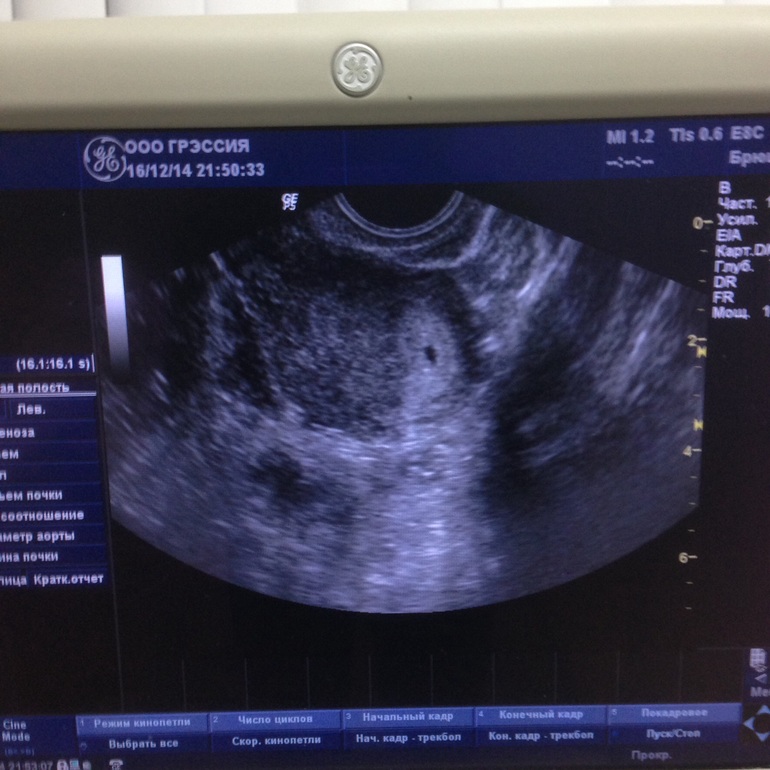

жду девочку, 8 неделя

Наше первое фото☺️

После работы сходила в душ и поехала на узи, все у нас хорошо